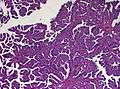

Choroid plexus papilloma, also known as papilloma of choroid plexus, is a rare benign neuroepithelial intraventricular WHO grade I lesion found in the choroid plexus.[1] It leads to increased cerebrospinal fluid production, thus causing increased intracranial pressure and hydrocephalus.[2]

The tumor is neuroectodermal in origin and similar in structure to a normal choroid plexus. They may be created by epithelial cells of the choroid plexus.